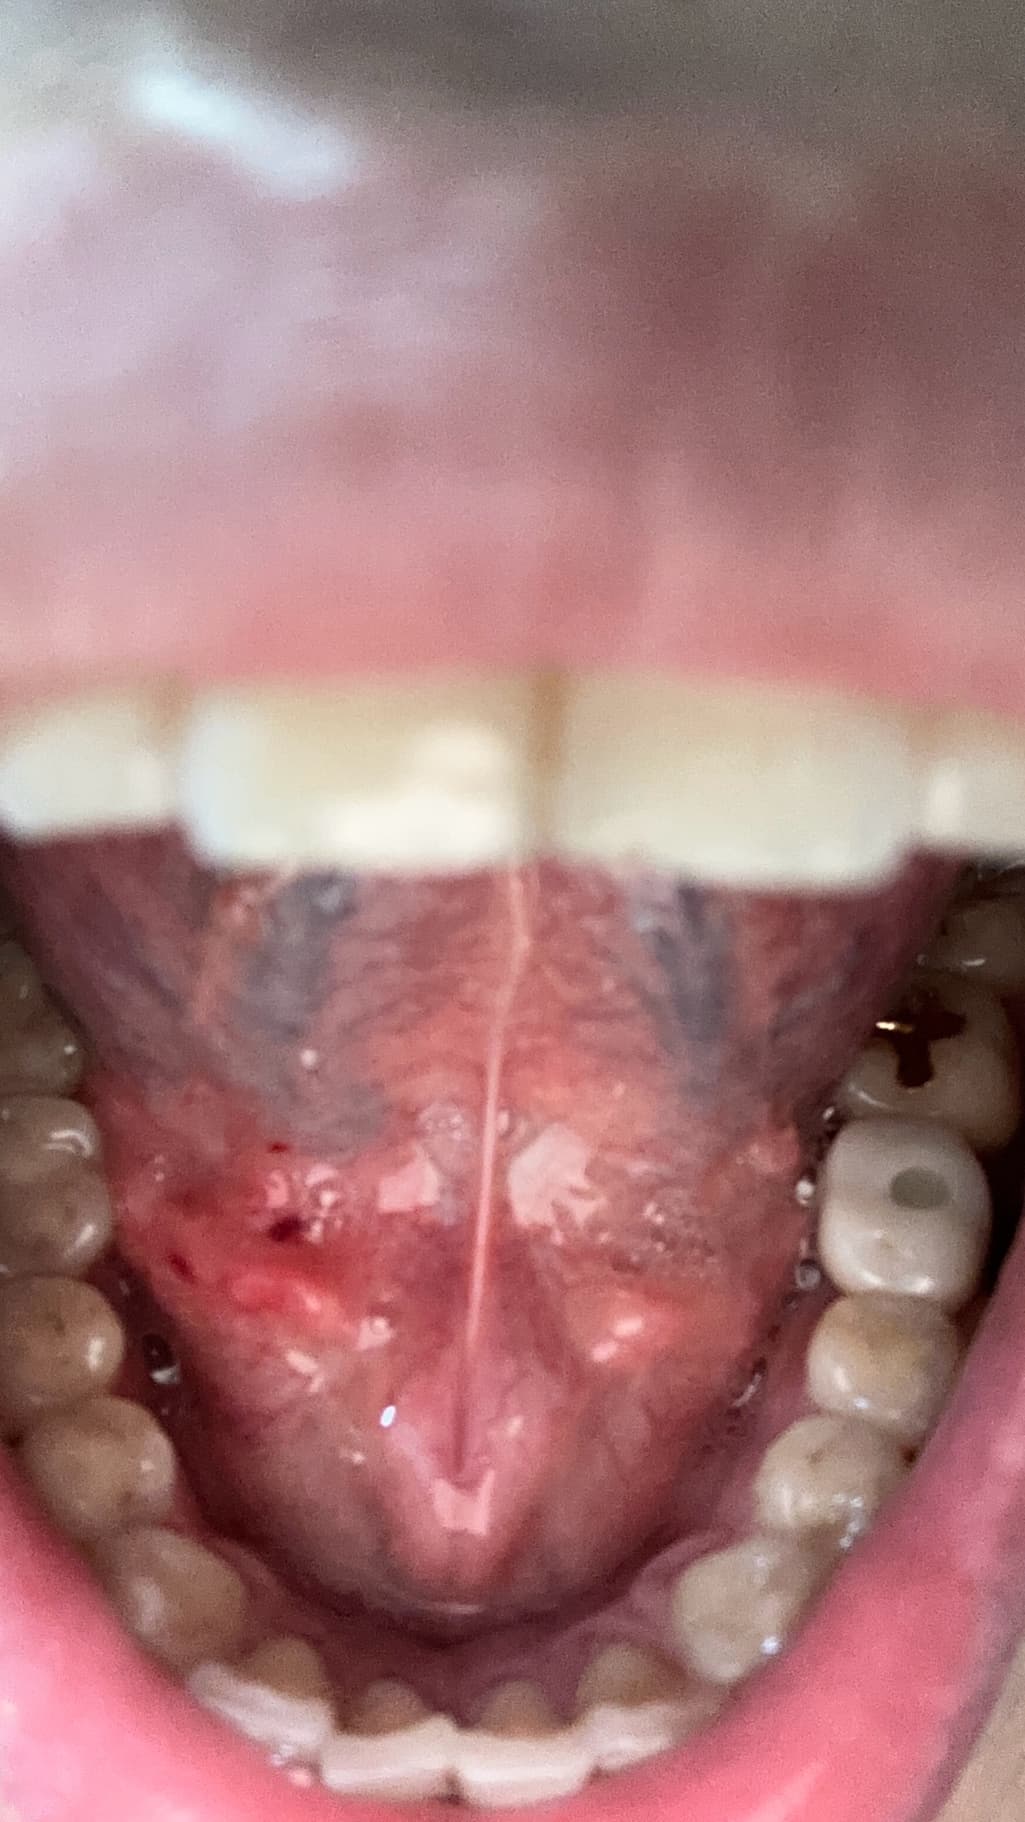

양치하다가 칫솔로 눌렀는데 피나는거처럼 됬어요

빨갛게 된부분이 있는것같고 그래서 이거 병원가봐야되는지 그냥 냅둬도 괜찮음지 궁금해요 어떻게하는게 좋을까요?? 병원은 무슨과인가요?

양치 중 칫솔로 인해 잇몸이 붉어지고 피가 나는 것은 잇몸 염증의 초기 증상일 수 있습니다. 칫솔질 시 잇몸에 과도한 힘이 가해지거나, 치석이나 치태가 쌓여 잇몸이 자극받았을 가능성이 있습니다. 우선 2~3일 정도는 부드러운 칫솔모를 사용하여 잇몸에 자극을 최소화하고, 치실이나 치간칫솔을 사용하여 꼼꼼하게 치아 사이를 청결하게 관리해주세요.

만약 며칠 후에도 증상이 호전되지 않거나, 붓기나 통증이 심해진다면 치과에 방문하여 정확한 진단을 받아보는 것이 좋습니다. 치과에서는 잇몸 상태를 확인하고 필요한 경우 스케일링이나 다른 치료를 통해 잇몸 건강을 회복할 수 있습니다.